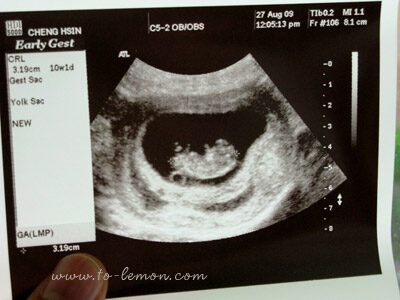

我們的三寶目前約10週大了!照超音波已經可以看到他手腳亂動的樣子,好可愛啊!額頭跟黎安小美一樣高高的……懷孕到現在也快三個月了!呼~還好快三個月了,希望害喜的情況會越來越減緩…….害喜讓我完全無法做想做的事,例如做飯,想吐的感覺跟餓的感覺會同時浮上來,有時加上像是暈車的感覺,不知道是不是因為生過兩胎了,這胎肚子大得像懷孕五六個月,早在兩個月時就被看出來懷孕了,真是不好意思…..不知道胎動會不會也提早感覺到~